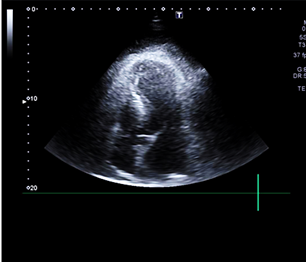

Initial echocardiography (Figure 5) showed severely reduced ejection fraction (LVEF =25%) with mid septal, apicoseptal, apical, apicolateral and mid lateral wall akinesia, representing the typical apical ballooning. The laboratory investigations showed Hemoglobin of 14,2mg/dl, electrolytes in normal range, slightly raised creatinine of 1,22mg/dl. Initial high sensitive Troponin T was 148pg/ml(ref=<14pg/ml)and peaked up to 2231 pg/ml next day (Figure 6).

Figure 5 Echocardiography.